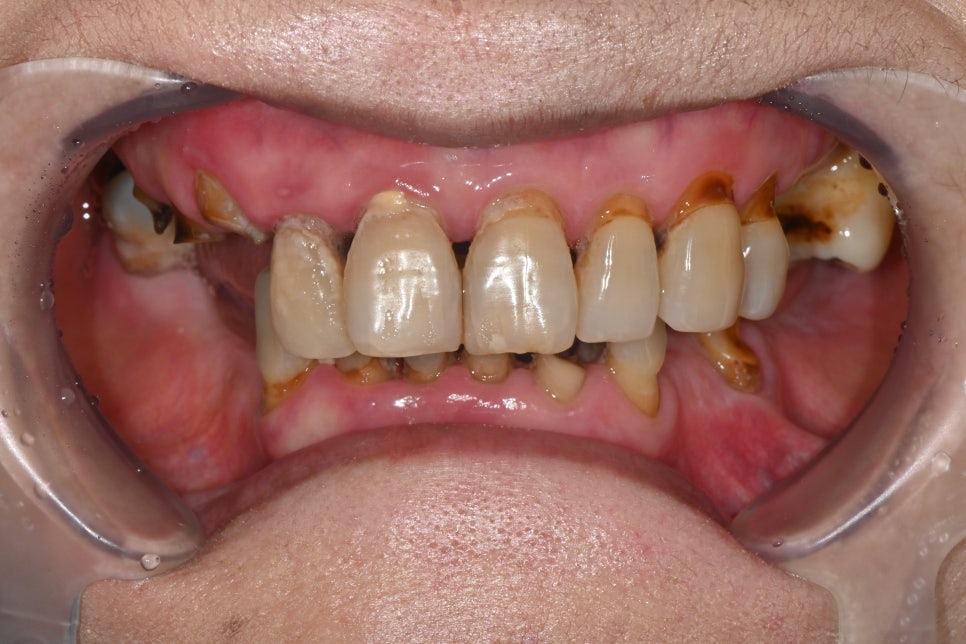

Condition at the Time of Visit

The patient had delayed dental care for more than 30 years,

and as a result, overall tooth wear, tooth loss, and gum inflammation

had developed together.

In particular, almost all molars were missing,

so chewing function had been lost,

and the remaining teeth were severely worn,

making it difficult to maintain the bite.

Food was repeatedly trapped between the gums,

causing recurring inflammation and odor,

and even everyday meals were very uncomfortable.